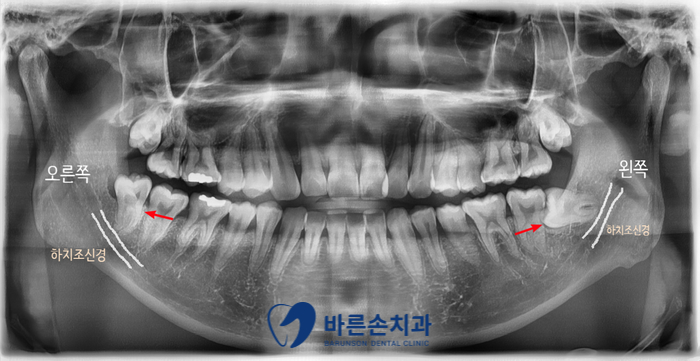

안녕하세요. <의정부 바른손치과>입니다.! 오늘은 사랑니 발치 증례를 보여드리도록 하겠습니다. 이 환자분은 20대 중반의 남성분으로 양쪽 아래 사랑니가 아프셔서 발치를 하러 저희 바른손치과를 찾아주셨습니다. 엑스레이 사진에서 보시면 양쪽 위 아래 사랑니가 모두 있고 왼쪽 아래 사랑니가 누워서 부분적으로 매복되어 있는 상태입니다. 구강 내 사진입니다. 좌우 모두 사랑니 머리가 일부만 구강내로 맹출해있습니다. 이런 경우 음식물이 끼기 쉽고, 칫솔로 제거도 쉽지가 않습니다. 그래서, 잇몸이 부어 피가 나고 아픈 경우가 자주 일어 날 수 있고 나아가 앞에 있는 치아 까지 썩게 할 수 있습니다ㅜㅜ 이런 경우엔 사랑니 발치를 통해 구강 환경 개선을 해야합니다!!! 사랑니 발치에 앞서 3D CT 촬영을 하였습니다. 사랑니의 형태와 위치, 아래턱뼈에 있는 하치조신경관의 해부학적 위치를 정확히 확인 후 발치에 들어갑니다. 오른쪽 아래 사랑니를 발치하고 엑스레이를 찍어 확인하였습니다. 왼쪽아래 옆으로 누워있는 사랑니도 발치를 하였습니다. 환자분께서는 문제를 일으키던 사랑니를 뽑으니 홀가분하고 시원하다고 하셨습니다.!! 약 일주일 정도 회복기간을 가지시면 사랑니 부위의 잇몸은 어느정도 아물게 됩니다. 사랑니 발치 더이상 두려워 하지 마시고 <의정부 바른손치과>에서 뽑으세요^^ |